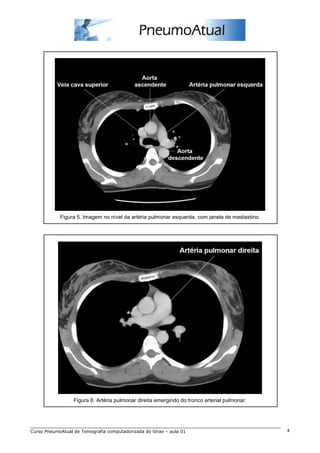

Figura 5. Imagem no nível da artéria pulmonar esquerda, com janela de mediastino.

Figura 6. Artéria pulmonar direita emergindo do tronco arterial pulmonar.

Figura 5. Imagemno nível da artéria pulmonar esquerda, com janela de mediastino. Figura 6. Artéria pulmonar direita emergindo do tronco arterial pulmonar. Curso PneumoAtual de Tomografia computadorizada do tórax – aula 01 4